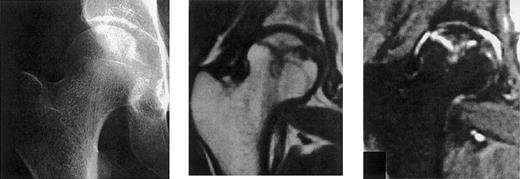

The published incidence of AVN varies from 4% to more than 10% in the largest series.83-87 The mean time from transplantation to AVN is 18 months (range, 4-132 months), and pain is usually the first sign. Early diagnosis can rarely be made using standard radiography alone, and magnetic resonance imaging is the investigation of choice (Figure 4). The hip is the affected site in more than 80% of cases, with bilateral involvement occurring in more than 60% cases. Other locations described include the knee (10% of patient with AVN), the wrist, and ankle. Symptomatic relief of pain and orthopedic measures to decrease the pressure on the affected joints are of value, but most adult patients with advanced damage will require surgery. The probability of total hip replacement following a diagnosis of AVN is approximately 80% at 5 years.88,89 Although short-term results of joint surgery are excellent in the majority (> 85%) of cases, it is clear that long-term follow-up of the protheses are needed in young patients who have a long life expectancy. Studies evaluating risk factors for AVN have clearly identified steroids (both total dose and duration) as the strongest risk factor. Thus, unnecessary long-term low-dose steroids for nonactive chronic GVHD should be avoided. The second major risk factor for AVN is TBI, the highest risks being associated with receipt of single doses of 10 Gy or higher or more than 12 Gy in fractionated doses.87 Finally, some underlying conditions may predispose a patient to develop AVN after SCT, in particular patients receiving transplants for severe aplastic anemia90 or acute lymphoblastic leukemia.

Avascular necrosis of the hip.

Standard radiography versus MRI as a tool for the diagnosis of avascular necrosis. These panels illustrate that standard radiography could be strictly normal at the first clinical sign while MRI is already highly abnormal. The top panel shows the normal appearance of the hip using standard radiography. The middle and bottom panels show 2 different MRI sequences showing that, although the femoral head is still spherical, the adjacent bone is already affected with necrosis, with even cartilage modification.